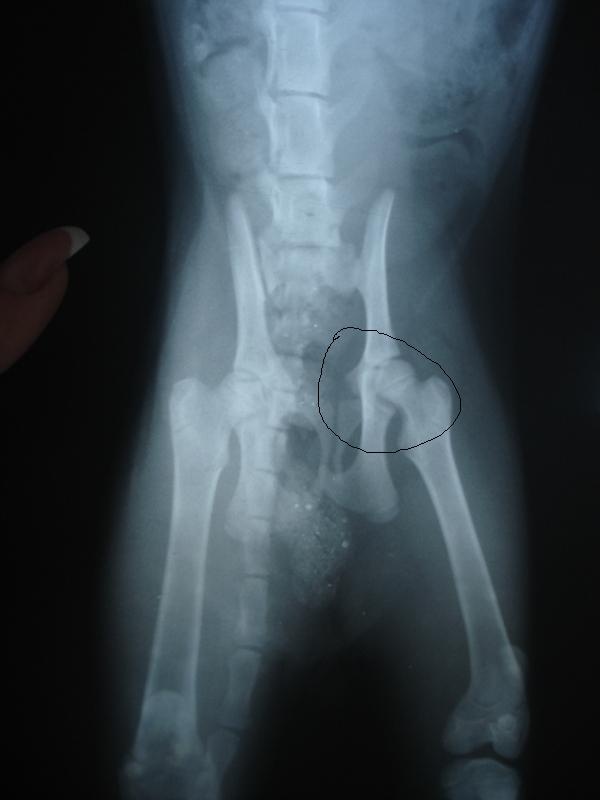

У меня все как обычно: пошла в магазин, смотрю по сторонам, вижу в сугробе, в самой глубине что-то черное......... пригляделась, котенок. Лежит, не шевелится, живой, но не вылазит. Вытащила, не ходит. Свозили ребенка в ЦВК на рентген, итог: Парень месяцев 5ти. Перелом заднего бедра, но он сам срастется сказали, сломаны зубы, но это не беда. Самое плохое то, что передняя лапка сломана и требует операции и как можно скорее. Локтевой бугор прям торчит в сторону. Нам необходимо ставить спицы. Стоит операция 7т.р. Я в данный момент не располагаю такой суммой, могу выделить на ребенка тысячи 2 максимум. Сейчас котенок временно поселился у моей подруги, принесла ему лежанку, он ее оценил, писает, какает, кушает с удовольствием. Снабдила ребенка кормом, наполнителем, мисками, лотком, лежаком. Но полную сумму на операцию я точно не потяну

Фото рентгена выложу завтра, т.к. щас темно и фото не получится, а завтра утром на окне сфоткаю. И котофея завтра по фотаю по лучше, сегодня все наспех как то.